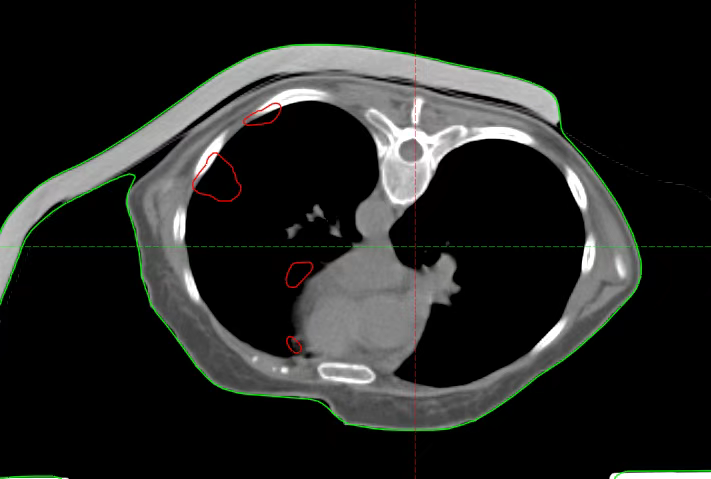

After admission, relevant examinations were completed. After excluding contraindications, radical carbon ion radiotherapy for recurrent thymoma was initiated on January 15, 2025. The radiotherapy doses were as follows: For the part of the left pleura far from the stomach and colon, 72 Gy (RBE)/18 Fx was administered; for the lesions adjacent to the heart border and esophagus, 52 Gy (RBE)/13 Fx was administered; for the part of the left pleura close to the stomach and colon, a basic dose of 40 Gy (RBE)/10 Fx was administered.

After Radical Regional Treatment